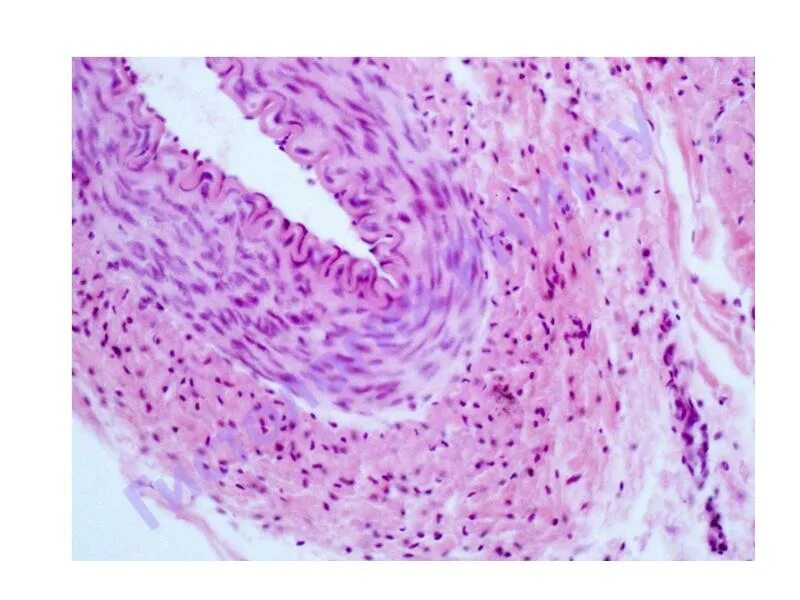

Артерия гистология препарат